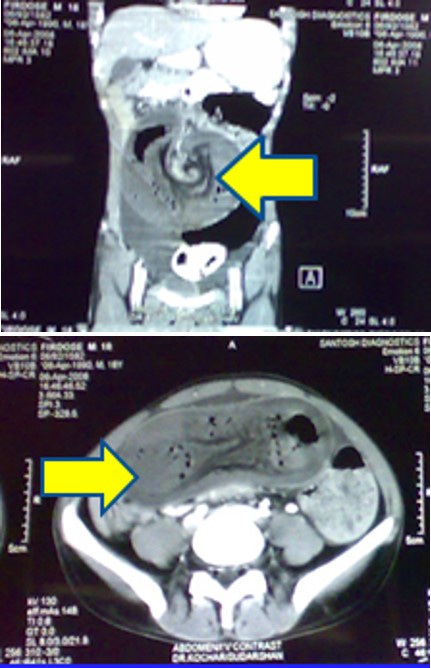

Computer tomograpahy:

• CT was done in 2 of our cases

• 1 case of PEUTZ JEGHERS SYNDROME

• 1 case was of chronic intussusception with benign polyp as lead point in ascending colon

Chronic intussusception:

• 12 years old female patient presented with chronic abdominal pain since 6 months.

• USG ABDOMEN-WNL.

• CT ABDOMEN.